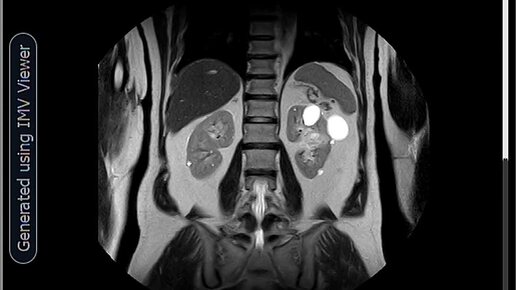

Множественные кисты почек.